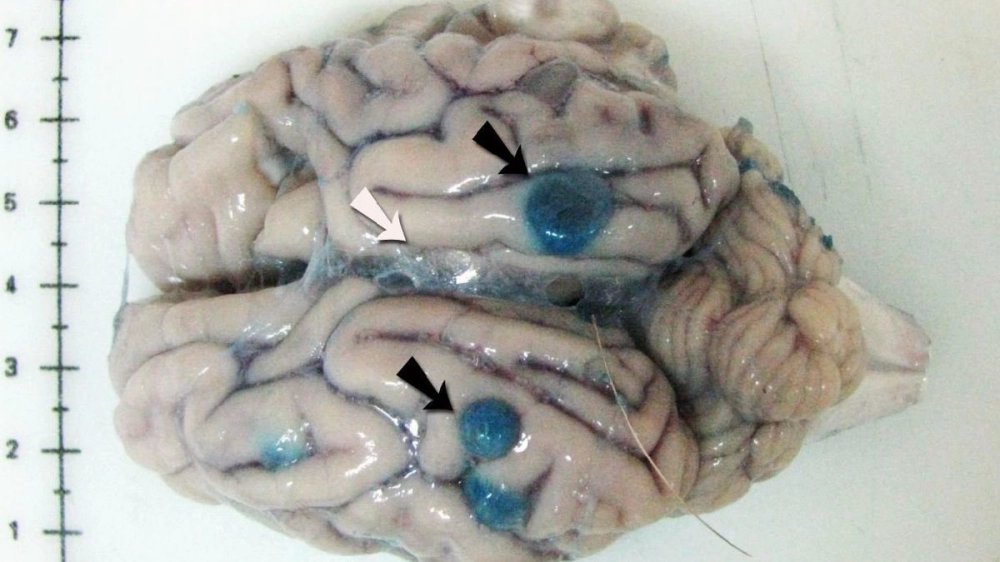

মুম্বইয়ের স্নায়ুরোগ বিশেষজ্ঞরা জানাচ্ছেন, বর্ষাকালে অনেকেই খাদ্যসুরক্ষা সংক্রান্ত সাধারণ নিয়ম মানেন না। তার ফলেই এই সংক্রমণের আশঙ্কা বেড়ে যায়। পেটে ঢুকে এই ডিম রক্তনালীর মাধ্যমে মস্তিষ্কে পৌঁছে যায় এবং সিস্ট তৈরি করে, যার ফলে শুরু হয় খিঁচুনি, ক্রমাগত মাথাব্যথা। চিকিৎসা সময় মতো শুরু না হলে স্নায়বিক অক্ষমতাও দেখা দিতে পারে।